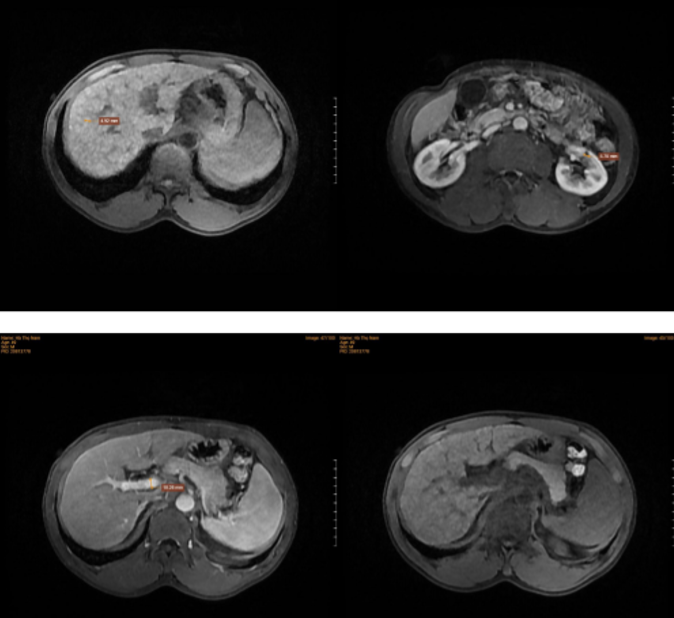

Chụp cộng hưởng từ tầng trên ổ bụng ghi nhận hình ảnh bất thường ở gan

Chụp cộng hưởng từ tầng trên ổ bụng ghi nhận hình ảnh các nốt tổn thương trong gan có ngấm thuốc tương đồng với nhu mô lành ở các thì tiêm thuốc hướng tới nốt tân tạo, trên nền xơ gan.